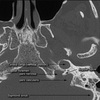

a, Labyrinthine segment; b, Greater superficial petrosal nerve; c, Cochlea; d, Geniculate ganglion; e, Stapes; f, Malleus; g, Incus; h, Tympanic segment of facial nerve; i, Vertical (mastoid) segment of facial nerve; j, Stylomastoid foramen; k, Horizontal (lateral) semicircular canal; l, Posterior semicircular canal; m, Superior semicircular canal; n, Inferior vestibular nerve; o, Superior vestibular nerve; p, Internal auditory canal; q, Facial nerve; r, Meatal foramen.